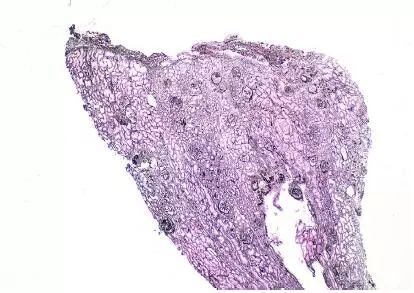

图6 CNI肾毒性条状肾间质纤维化(Jones 银染)

CNI肾毒性导致的血管收缩无形态学变化。急性CNI肾毒性特征包括:近端肾小管上皮细胞空泡化,大小一致;血管损伤,平滑肌细胞丢失;肌细胞胞浆空泡化;细胞坏死或凋亡退化。肌细胞损伤最终发展为局灶性结节性玻璃样变和透明样变,可延伸至小动脉和动脉血管壁整个中层。CNI肾毒性还可引起血栓性微血管病变(TMA),主要累及小动脉和肾小球毛细血管袢。慢性CNI毒性特征为:条状间质纤维化,肾小管萎缩。